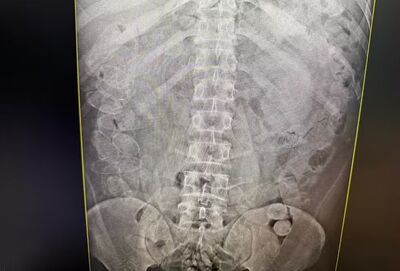

Três confessaram ter engolido cerca de 86 cápsulas cada um. Foto: Receita Federal Três confessaram ter engolido cerca de 86 cápsulas cada um. Foto: Receita Federal

Diante da suspeita de que os demais homens pudessem ter ingerido a droga, os quatro foram encaminhados para um hospital da cidade, onde passaram por exames de raio X.

Um deles afirmou que não conseguiu engolir as cápsulas e que todo o material encontrado com ele era de sua responsabilidade. Já os outros três confessaram ter engolido cerca de 86 cápsulas cada um.